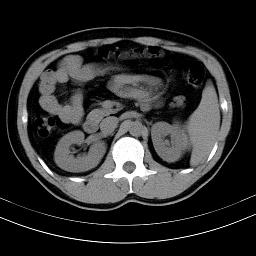

标题: CT18388:肝脏膈肌间隙内大量脂肪密度影 [打印本页]

标题: CT18388:肝脏膈肌间隙内大量脂肪密度影

考虑----气腹可能性大---进一步检查

是脂肪不是气体,有时候会碰到这样的病人,脂肪过多吧。

腹腔脂肪沉积过多

局部脂肪沉积。

膈下脂肪沉积。

考虑膈下脂肪沉积。

腹腔脂肪沉积症

激素治疗的病人容易脂肪沉积